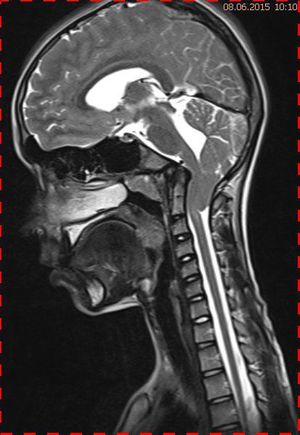

Abb. 2.1 Sagittales MRT (T2 TSE, 1,5 T): bei unveränderter Streckfehlhaltung der HWS 2 Monate nach der Erstuntersuchung Progredienz des Tonsillentiefstands, Syringomyelie

Trotz weiterer Schmerz- und Physiotherapie konnte keine Beschwerdereduktion erreicht werden. 2 Monate später erfolgte eine MRT des Kopfes zum Ausschluss einer posttraumatischen Veränderung.

Bei dieser Untersuchung wurde übersehen, dass die Kleinhirntonsillen in das Foramen magnum disloziert waren und eine Arnold-Chiari-Malformation mit Erweiterung des 4. Ventrikels und des Aquäduktes inklusive Kleinhirntonsillentiefstand vorlag. Bei zwischenzeitlich auswärtig erfolgtem CT der HWS wurde eine Anlagestörung im kraniozervikalen Übergang beschrieben. Eine Kontrolluntersuchung des Kopfes weitere 4 Monate später dokumentierte neben einem medullären Ödem einen progredienten Tonsillentiefstand, der zur neurochirurgischen Behandlung mit operativer Erweiterung des Foramen magnum führte.